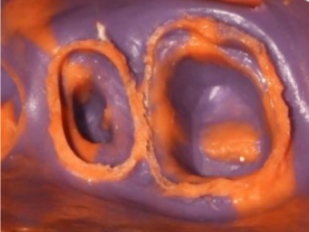

Step 6: Take the precise impression

Use PERFIT impression products for precise impression taking . HUGE offers impression materials with various viscosities and curing speeds.

*Note the fluidity of the material in the gingival sulcus after gingival displacement with a retraction cord, achieving an excellent replica of the entire dental perimeter.